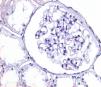

ResultsOf the 90 cases studied, a total of 36 men (40%) and 54 women (60%) were used. The age range found was very broad, from 3 years to 66 years. The age distribution was divided into age groups, each corresponding to one decade of life. The largest number of cases (35.55%) occurred in the second decade of life (11–20 years) followed by the first decade (28.88%). In order to separate the two large entities that share the morphological pattern of GBM structural disorders, TBMD and ultrastructural changes compatible with AS, the TEM findings were used, since in our environment there is no specific immunoreactant for each one of the type IV collagen chains to classify each of the variants. In AS, the TEM findings are the multilamination of the GBM dense lamina, which confers an “interwoven” or “basket-like” appearance. In addition, it is possible to observe microparticles in the GBM or “bread crumbs” between the laminations, a scalloped section or “excrescence” of the subepithelial surface of the GBM and a variable and irregular thickness, both thick and thin GBMs, unlike TBMD, where thinning is uniform and homogeneous (>50% of GBMs) and measure <200nm in thickness. In this way, 38 cases (42.22%) were compatible with TBMD and 52 cases (57.77%) with ultrastructural changes suggestive of AS.

Of the 52 cases with characteristics compatible with AS, the majority were men (29 cases, 55.76%). The age of the patients ranged from 3 to 39 years; the majority (23 cases) were detected in the second decade of life (44.23%), with a mean of 14 years. The findings on clinical presentation, glomerular lesions overloaded with the pattern of structural changes in GBM, degree of interstitial fibrosis and associated tubular atrophy and degree of arteriolopathy are shown in Table 1. It should be noted that a history of auditory and/or visual alterations (neurosensorial deafness, corneal opacities, etc.) were reported in only 5 cases (9.61%). In the histopathological study of the cases with characteristics compatible with AS, minimal changes were observed in the glomeruli. Most of them were anodyne (36.53%), with folded and laminated GBM segments, alternating with others with “thin” appearance and only 6 cases (11.53%) showed mild mesangial hypercellularity, especially in younger patients. The interstitial foamy macrophages were only present in those cases with a history of proteinuria. The direct immunofluorescence study was negative for all the immunoreactants that are routinely analysed (IgG, IgA, IgM, C1q, C3c, C4c, Fibrinogen, Albumin, Kappa and Lambda). Deposits were only detected by entrapment in those glomeruli with zones of segmental sclerosis (non-specific deposit). On average, the GBMs of cases with AS measured 245.27nm, a lower than expected average for the normal thickness of glomerular basement membranes in adults. However, it is necessary to take into account the number of patients under 11 years of age and the heterogeneous nature of the measurements, since an average minimum measurement of 132.16nm and an average maximum measurement of 464.96nm were found, with measurements as thin as 57nm to thick segments of 1039nm. This explains the irregularity of the membranes in this entity (Fig. 1) and by definition they cannot be pigeonholed as TBMD.